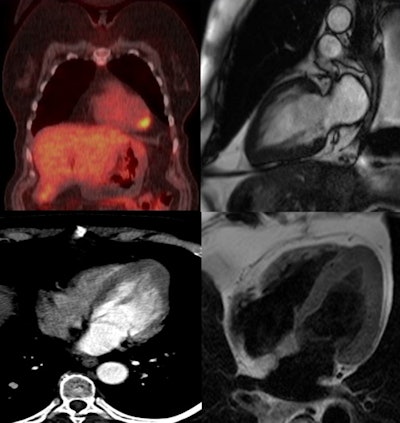

At the Milan meeting, Gezmis reported about the case of a lung cancer patient with focal cardiac FDG uptake on whole-body oncological PET/CT, which turned out to reflect apical HCM when further evaluated with CMR.

A subsequent whole-body FDG-PET/CT scan showed uptake in the mass and right hilar lymph node, confirming the diagnosis, but increased focal activity was also noted at the apex of the left ventricle, which appeared to be within the wall rather than the lumen. This raised the possibility of cardiac metastasis, which would have changed the management of the patient, and further evaluation was required.

Despite the fact it was not ECG-gated, the thoracic CT scan was reassessed regarding the heart by putting the images into true cardiac planes using multiplanar reconstruction. This demonstrated the loss of tapering of myocardium from the base to the apex with thickening of distal walls, suggesting apical HCM.

Contrast-enhanced cardiac MRI was performed to rule out metastasis and validate the apical HCM diagnosis. The images showed disproportionate and focal wall thickening in the left ventricular apex, which corresponded with the area of avidity on the PET/CT scan. There was also a "spade-like" configuration of the apical left ventricular cavity, and contractility of myocardium was preserved.

Dr. Stephen Harden.

"No mass or gadolinium enhancement was noted and the appearance was in keeping with an apical hypertrophic cardiomyopathy phenotype. The pathology test results from the CT-guided biopsy of the lung mass and subsequently performed right lower lobectomy were adenocarcinoma. The benefit of chemotherapy was outweighed by risk and the patient has been under follow-up since then," Gezmis concluded.